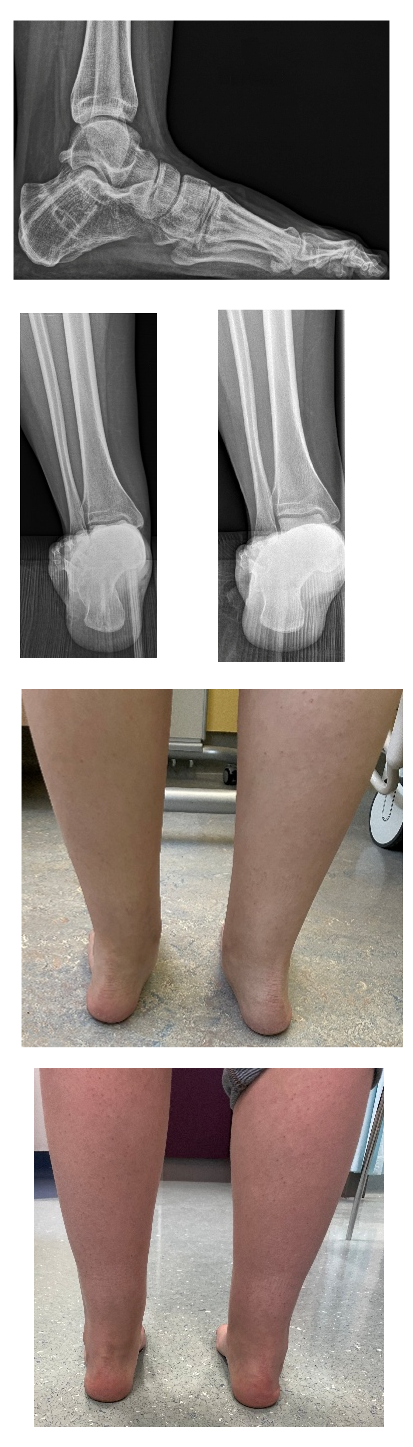

Results: Complete union was recorded after 3.6 months and 4.5 months for the human allogeneic cortical bone screw (Figure 1 [Abb. 1]) and Metal/Biotenodesis group, respectively. PROM’s of 27 patients after 1-year and 11 patients after 2-years are shown in the Table 1 [Tab. 1]. For both groups, the PROM’s improved. Table 1 [Tab. 1] shows that the allogeneic bone screw group tend to achieve better results earlier, for all PROM’s. A total of 11 implant removals (33%) were performed in the Metal/Biotenodesis group.

Figure 1: Pre-and postsurgery Xray and clinical pictures